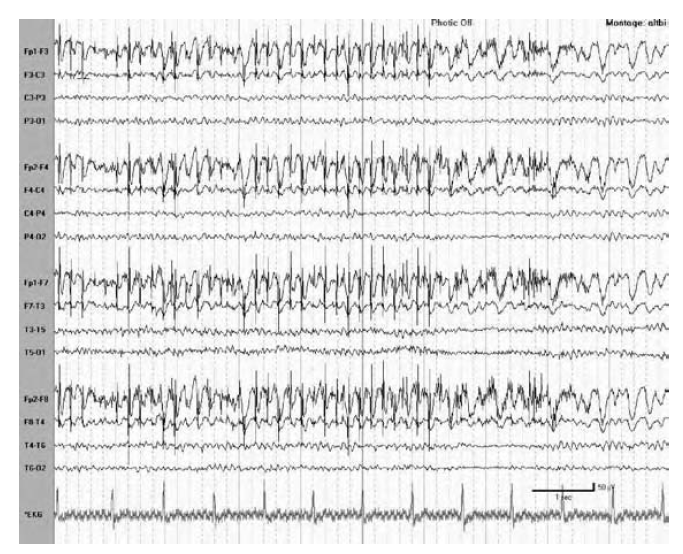

WHAT ARTIFACT IS SEEN

Artifact from three horizontal eye movements (looking left) followed by two vertical eye blinks.

During drowsiness, slow rolling (lateral) eye movements are similarly helpful. Lateral eye movements are usually easily recognized because they create phase reversals in the anterior temporal derivations that are of opposite polarity on opposite sides of the scalp EEG.